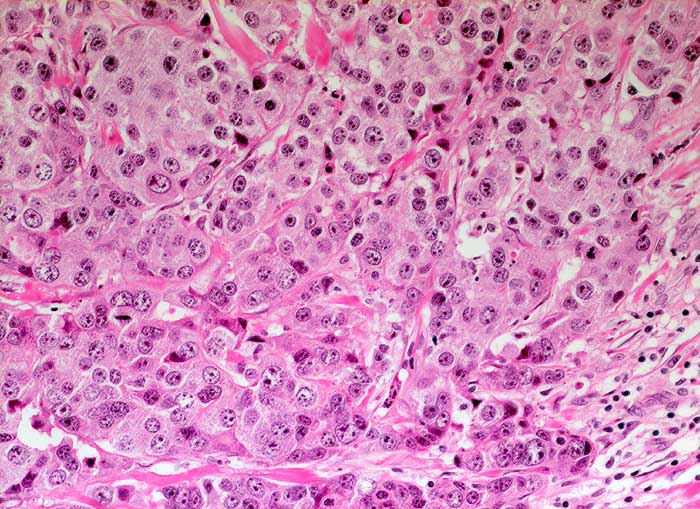

Wenig differenziertes invasiv duktales Mammakarzinom

Trabekulär angeordnete stark atypische Tumorzellen mit deutlicher Pleomorphie und hyperchromatischen Kernen. Reichlich eosinophiles Zytoplasma.